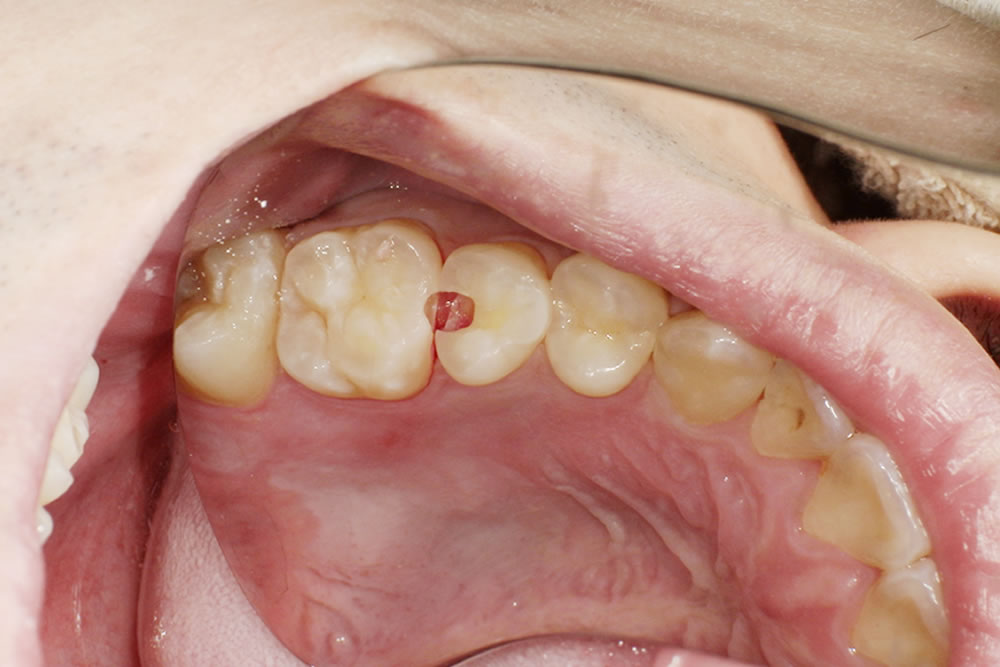

こちらの患者さまは以前から当院に通院されている方で、定期的な通院の中で今回の虫歯が見つかりました。

来院時のお口の状態

診査とレントゲン検査の結果、左上の奥歯(左上5番)の歯と歯の間に虫歯が認められました。歯と歯の間の虫歯は見た目では分かりにくいことが多く、レントゲン検査で発見されることも少なくありません。

患者さまはホワイトニングも行っているため、「なるべく目立たない、自然な見た目のつめ物で治療したい」というご希望がありました。

セラミックインレー・CRによる修復

今回は経過観察中に特に症状が現れなかったため、患者さまと相談のうえセラミックインレー(セラミックのつめ物)で治療を行いました。

セラミックは透明感があり、天然歯に近い自然な見た目に仕上げることができます。また表面がなめらかで汚れが付きにくく、二次虫歯(詰め物の周囲に再びできる虫歯)のリスクを抑えるという特徴があります。

なお、隣の歯には浅く小さな虫歯が確認されたため、その部分のみを削り、CR(コンポジットレジン)という白い樹脂材料で修復を行いました。